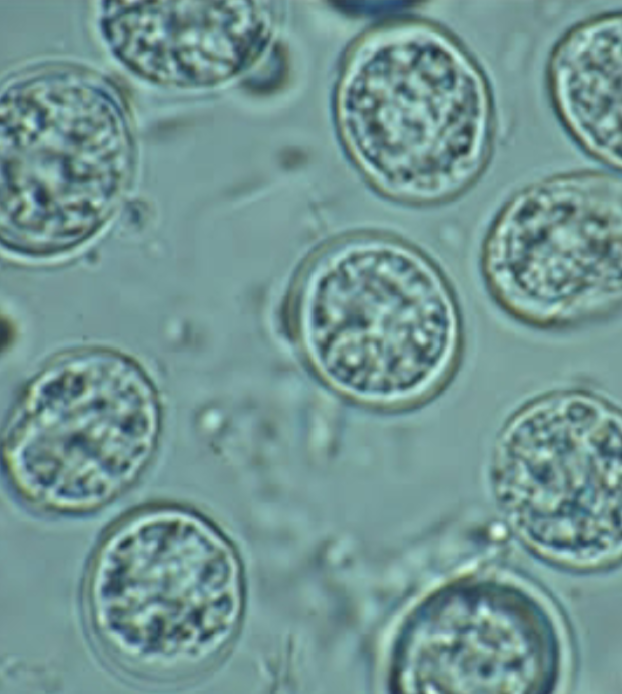

Cyclospora cayetanensis